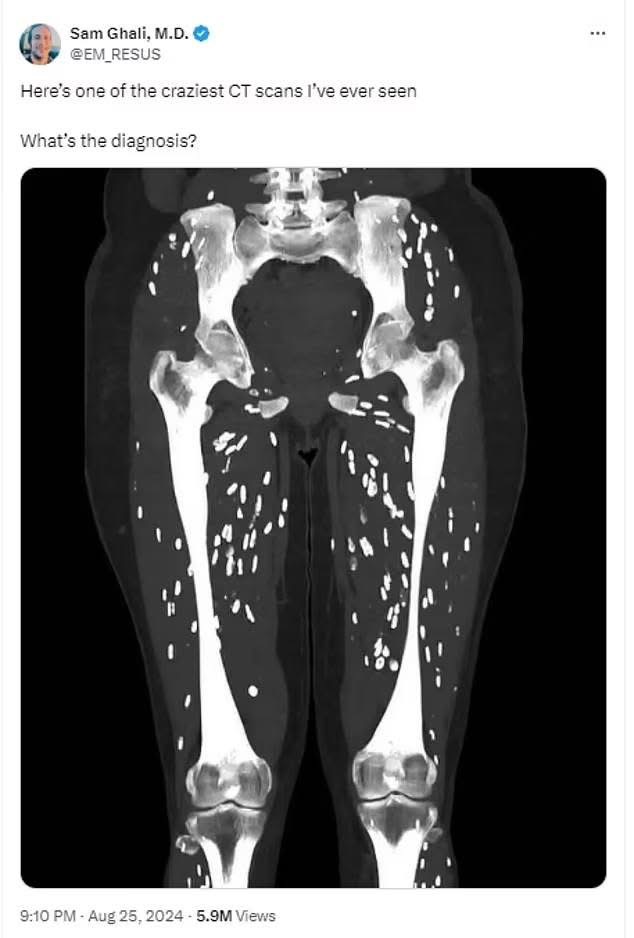

Rreziqet e ngrënies së mishit të derrit të papjekur janë zbuluar në një skanim të trupit që tregon parazitët që mund të infektojnë trupin përmes mishit të kontaminuar.

Dr Sam Ghali, një mjek i kujdesit urgjent nga Universiteti i Floridës , shkroi në mediat sociale për të ndarë një imazh të një pacienti me shenja treguese të një infeksioni parazitar të quajtur cisticerkozë dhe demete e konsumimit te mishit te derrit.

Cisticerkoza ndodh kur larvat e një lloji të krimbit të shiritit hyjnë në inde si muskuli apo edhe truri.

Ata formojnë një kist të fortë të kalcifikuar që mund të ndihet si gunga nën lëkurë dhe ndizet si nyje të bardha ovale ‘kokrra orizi’ në skanimet mjekësore.

Dr Ghali shtoi: ’50 milionë njerëz në mbarë botën infektohen çdo vit me kete lloj semundje dhe rreth 50,000 persona humbin jeten nga kjo lloj semundje.

“Pra, morali i historisë këtu është të bëni më të mirën tuaj për të mbajtur pastërtinë, lani gjithmonë duart dhe kurrë mos hani mish derri të papërpunuar ose të papjekur apo qendroni larg ketij mishi.” SHIKO.NEWS